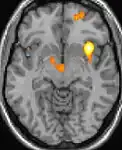

| Voxel-based morphometry (VBM) shows brain area structural differences | ||

Positron emission tomography (PET) scans indicate the brain areas which are activated during attack only, compared to pain free periods. These pictures show brain areas that are active during pain in yellow/orange color (called "pain matrix"). The area in the center (in all three views) is specifically activated during CH only. The bottom row voxel-based morphometry (VBM) shows structural brain differences between individuals with and without CH; only a portion of the hypothalamus is different.[33]